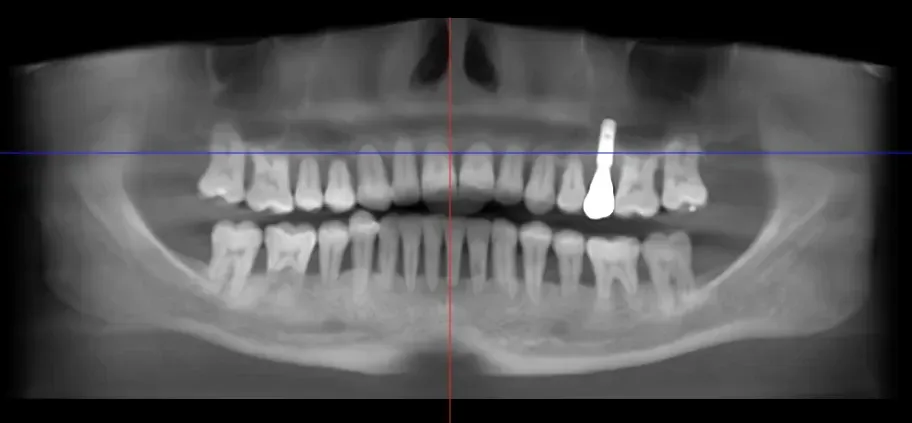

So here is today’s example of a tooth with a failing silver/amalgam filling (decay around the edges and deep cracks that could have led to the tooth breaking at an inconvenient time) replaced with a gold onlay:

Family dentist Dr. Charles Payet used a gold onlay to fix a cracked tooth that had an old silver filling.

The gentleman who chose this is around 40 years old, and with regular dental care and the same excellent home care he has, this tooth and gold onlay will probably last until he is no longer in need of teeth any longer.